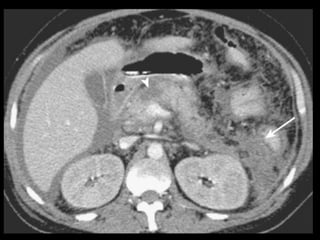

Complicações da PA

1. Coleções líquidas agudas

2. Abscesso pancreático

3. Necrose

4. Hemorragia

Coleções líquidas agudas

Ocorrem em cerca de 40% dos casos;

Podem ser em torno da glândula ou extra-

pancreático;

Carecem de cápsula e são confinadas ao espaço

anatômico onde se encontram;

Podem dissecar para outros locais: mediastino,

pararrenal posterior, órgãos sólidos ou parede de

alça intestinal.

Coleções líquidas agudas- TC

Hipodensas

Mal definidas

Sem cápsula ou parede reconhecível

Resolução espontânea em 50% dos casos;

Complicações: dor, infecção secundária e

hemorragia;

São passíveis de drenagem percutânea caso não

regridam ou se tornem infectadas.